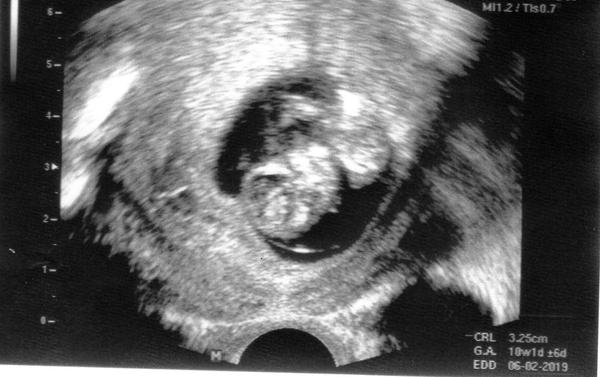

@skretik Ja uz se ode dneska nebudu stresovat. Na kontrole rano mimi odpovidalo velikosti, takze vsechno zatim vypada dobre. Uz nevypada jako disko sroub, ale clovek.. tak se hodim do klidu 🙂